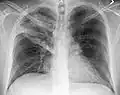

Normal lateral CXR -

The discovery of x-rays made it possible to determine the anatomic type of pneumonia without direct examination of the lungs at autopsy and led to the development of a radiological classification. Early investigators distinguished between typical lobar pneumonia and atypical (e.g. Chlamydophila) or viral pneumonia using the location, distribution, and appearance of the opacities they saw on chest x-rays. Certain x-ray findings can be used to help predict the course of illness, although it is not possible to clearly determine the microbiologic cause of a pneumonia with x-rays alone.